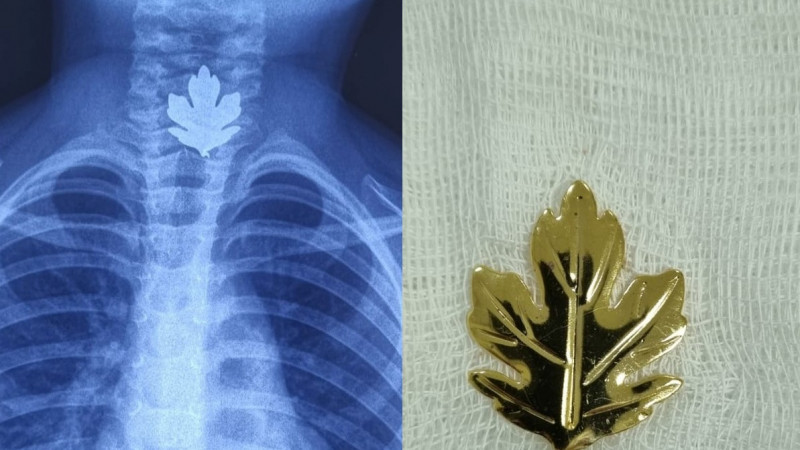

Назван вид рака, который хуже всего поддается лечению

Хуже всего поддаются лечению раковые опухоли, обнаруженные на последних стадиях. Также назван вид онкологии, который лечить труднее всего, передает